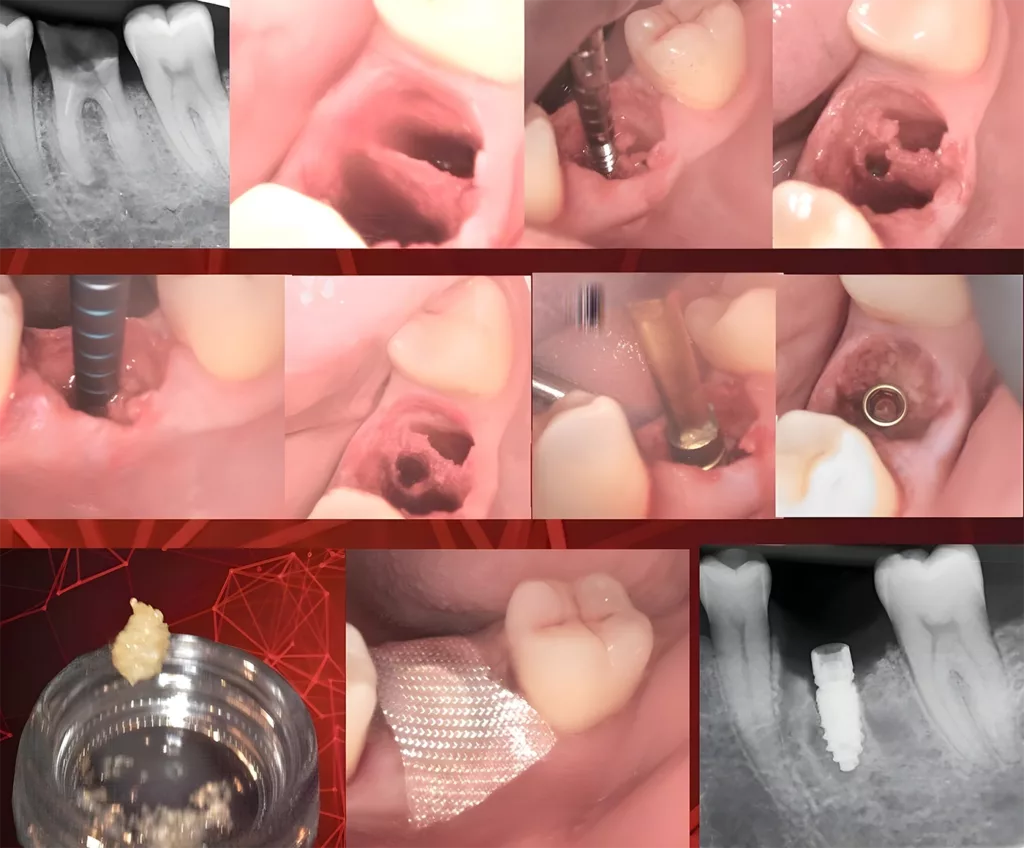

Sofortimplantate gehören dank MIMI inzwischen zum täglichen Prozedere in meinen Praxen: Nach schonender Extraktion des Zahnes 36 wurde in diesem Fall ein zweiteiliges Champions (R)Evolution Implantat (Länge: 10 mm, Durchmesser: 4 mm) inseriert. Parallel erfolgte die Aufbereitung des Zahnes 36 im Smart Grinder-Verfahren (Kometabio), da das Zahnmaterial mehr Knochenwachstumsfaktoren (BMPs) als der Knochen selbst aufweist. Das so gewonnene autologe Material wird direkt nach der Rö2-Implantationskontrolle krestal in die Restalveole platziert und mit einem BloodStop-Pflaster gesichert. Durch das „Pflaster“, welches sich bereits nach drei Minuten zu einem klebrigen, transparenten Gel verwandelt und nach 48 Stunden vollständig resorbiert, entfällt eine Naht. Die Kronen werden bei solchen „Sofis“ nach ca. vier Monaten eingegliedert (Abb. 2).

Zur Fixierung einer unteren Totalprothese wurden innerhalb von 75 Minuten vier Implantate interforaminal mit MIMI und einteiligen Kugelkopf-Champions inkorporiert und die MMT-Matrizen in Sofortbelastung in die Prothese eingearbeitet (Abb. 3).

Auch interne, direkte Sinuslifte (IDS) sind mit MIMI problemlos möglich. Mit konischen Dreikantbohrern und inzwischen fast nur noch „digital“ wird die Gegenkortikalis des Kieferhöhlenbodens „aufgespürt“ und mit abgeflachten WS-Condensern mit 30 U/Min. und 30 bis 40 Ncm eröffnet, um die Schneidersche Membran bis zu 5 mm unkompliziert mit Knochenersatzmaterial (Smart Grinder oder Ethoss) anzuheben. Diese MIMI-VI-Implantation kann man simultan mit dem IDS durchführen, wenn mindestens 3 mm Restknochenhöhe vorhanden ist. Dabei sollte man allerdings nicht, wie sonst empfohlen, 1 bis 2 mm subkrestal implantieren, sondern äquikrestal, d.h. auf „Bone-Level“, damit das Mikrogewinde des Champions voll in der Restknochenhöhe gefasst ist. Auch in IDS-Fällen warten wir mindestens vier Monate bis zum Einsetzen der Krone (Abb. 4).